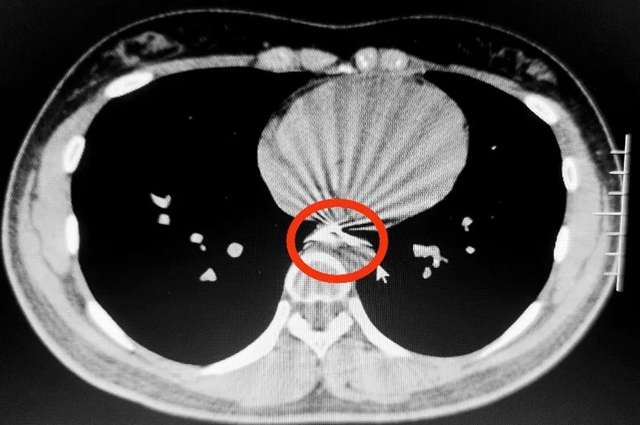

急诊科何文扬医生立即联系了正在上门诊的消化内科副主任(主持工作)钟晓琳教授。为了明确异物的情况,影像科立即为女孩拍了CT片,发现这颗牙套长约3厘米,带有弯曲的钢丝,卡在了食管中段狭窄处(心脏水平)。

更可怕的是,从影像片子上看,牙套上的钢丝可能已经刺破食道,紧邻主动脉,又由于金属在摄片时会产生伪影,很难判断钢丝尖端和主动脉的关系,不除外已经穿入主动脉的可能。